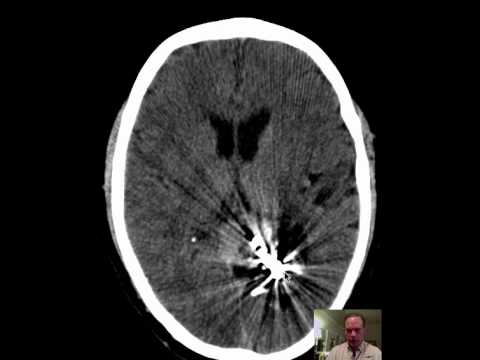

Hellow guys, Welcome to my website, and you are watching Supracerebellar-Infratentorial Approach for a Posterior Midbrain Arteriovenous Malformation (AVM). and this vIdeo is uploaded by Barrow Neurological Institute at 2021-07-01T12:35:23-07:00. We are pramote this video only for entertainment and educational perpose only. So, I hop you like our website.